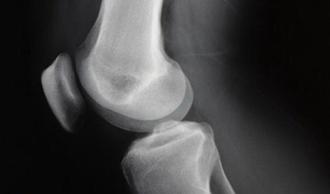

Fractura de estrés del fémur

La aparición de cualquier solución de continuidad (fractura) en el hueso del muslo (fémur).